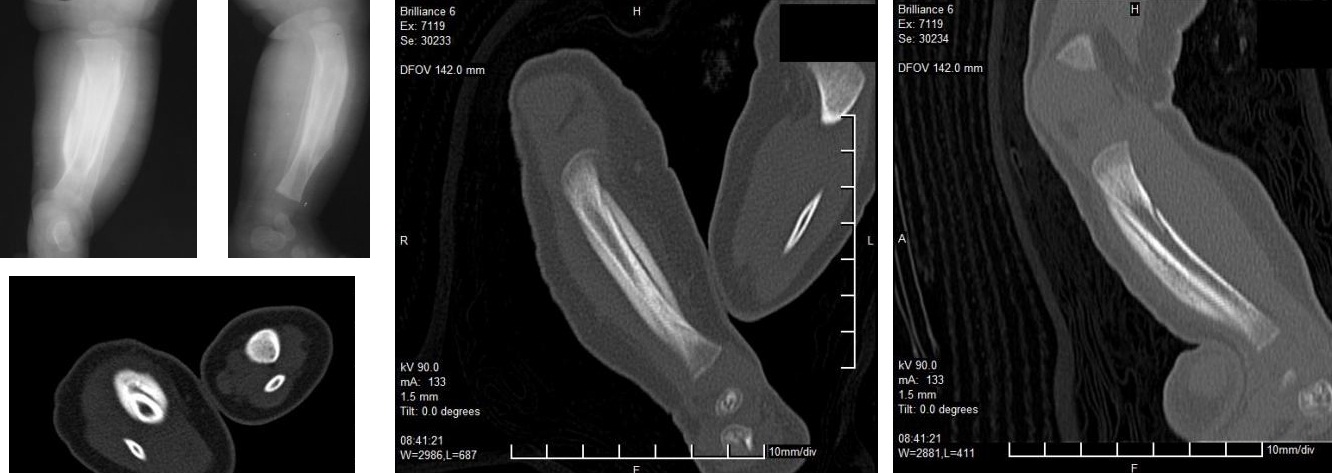

При врожденном заболевании Камурати-Энгельманна наблюдается ограничение подвижности в бедренных и плечевых суставах. В этих областях, а также в большеберцовых костях, возникают интенсивные болевые ощущения. Мышечная масса остается недостаточно развитой. В редких случаях может происходить поражение затылочной области и нарушения в формировании свода черепа у ребенка. Теменные кости срастаются быстрее, чем обычно. Часто наблюдается характерная «утинная» походка.

Эти изменения могут вызывать болевые ощущения и дискомфорт у ребенка. Также возможно уплотнение трубчатых костей, ключиц и искривление большеберцовых костей.

- рентгенография;

- компьютерная томография (КТ);

- магнитно-резонансная томография (МРТ);